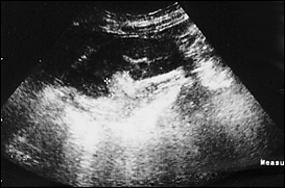

Ecografia vezicii urinare se poate executa pe cale abdominala, transrectala sau transuretrala. Tumorile vezicale apar la ecografie ca mase exofitice, ecodense, intracavitare, fixate la perete, care nu-si schimba pozitia odata cu schimbarea pozitiei pacientului, cu perete vezical normal adiacent tumorii.

a. b.

Figura 34. a,b. Aspecte ecografice de tumora vezicala - transductor abdominal.

Figura 3 a,b) Aspecte ecografice de tumori vezicale. Formatiuni exofitice protruzive intravezicale.

Unele studii acorda ecografiei posibilitatea de a diagnostica o tumora vezicala in proportie de 80% [85]. Cu toate acestea, ea nu poate pune diagnostic de certitudine, ci completeaza celelalte investigatii.